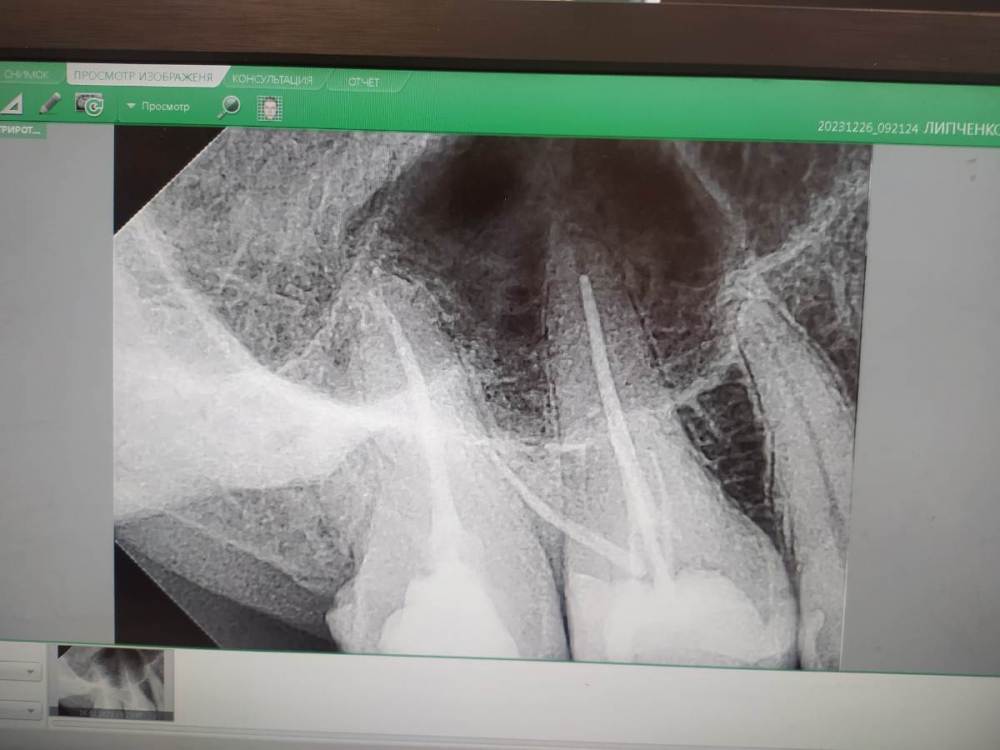

Pик Опубликовано 27 декабря, 2023 Поделиться Опубликовано 27 декабря, 2023 (изменено) Доброй ночи. Обратился в стоматологическую поликлинику. Обнаружили пульпит верхней 6 справа. Врач определил по рентгену что 6ка - 3 х канальная, до этого мне другой врач в этой стоматологии направлял на к-т и бегло посмотрев сказал что у меня периодонтит, о чем я уже сообщил лечащему. Врач удивился сказал что на рентгене этого не видит, возможно из за пазухи носа. Заложили кальций. Через 3 дня я взвыл и в выходной помчал к дежурному врачу. Сказали бывает реакция на кальций и поменяли на депульпин или похожее название. Зуб стал успокаиваться... На следующем приёме, после извлечения лекарства , стоматолог усомнился в количестве каналов и в итоге обнаружил ещё 1 канал - 4ый ! Всё по новой, заложили кальций. Через уже 2 дня произошло всё тоже самое. Опять меняем лекарство на депульпин. Тут стоматолог предположил что трещина под десной и всё таки воспаление не в каналах а между корнями.... Ждём неделю. Я параллельно иду ещё на консультацию, там делают рентген, говорят что всё в порядке воспаления не видят вообще . Зуб не болит при постукивании, при надкусывание - а только иногда дёргает, как иголочки. Говорят должно пройти. Буквально 3 дня назад запломбировали каналы. Пломбу ещё не ставили. Склоняюсь к удалению, потому что зуб все так же дёргает ... При надкусывании и постукивании не болит.! И вот на работе разговорился с коллегой, она поведала историю что у неё в одном зубе обнаружили 6 каналов. Ради интереса полез сам на к-т. Послушал видео урок как что смотреть. Обнаружил вот это. Причём такое наблюдаю только на этом зубе. Зуб,к слову очень необычной формы, какой то большой продолговатый, со скаловидным дефектом. Подскажите может и правда это тот случай когда есть ещё 2 канала, которые не заметил врач. К-т сделано до пломбировки каналов. P. S. то что надо менять клинику понимаю, но я пришёл в государственную на платной основе... Изменено 27 декабря, 2023 пользователем Pик Плохое качество снимка Ссылка на комментарий

Pик Опубликовано 28 декабря, 2023 Автор Поделиться Опубликовано 28 декабря, 2023 Добавляю снимок запломбированного зуба. Может тут что то видно Ссылка на комментарий